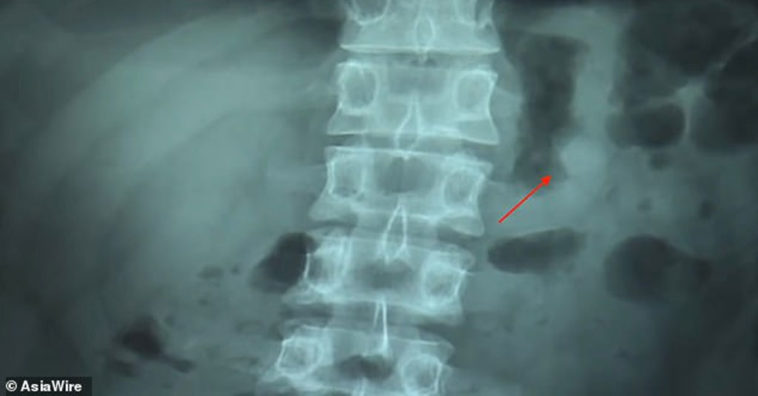

แพทย์ได้ทำการ X-Rey พบว่า AirPods หนึ่งข้างติดอยู่ในท้องของหนุ่มใต้หวัน หลังจากนั้นก็ใช้วิธีธรรรมชาติขับถ่าย AirPods ออกมาปรากฏว่าตัวหูฟังยังใช้งานได้อยู่